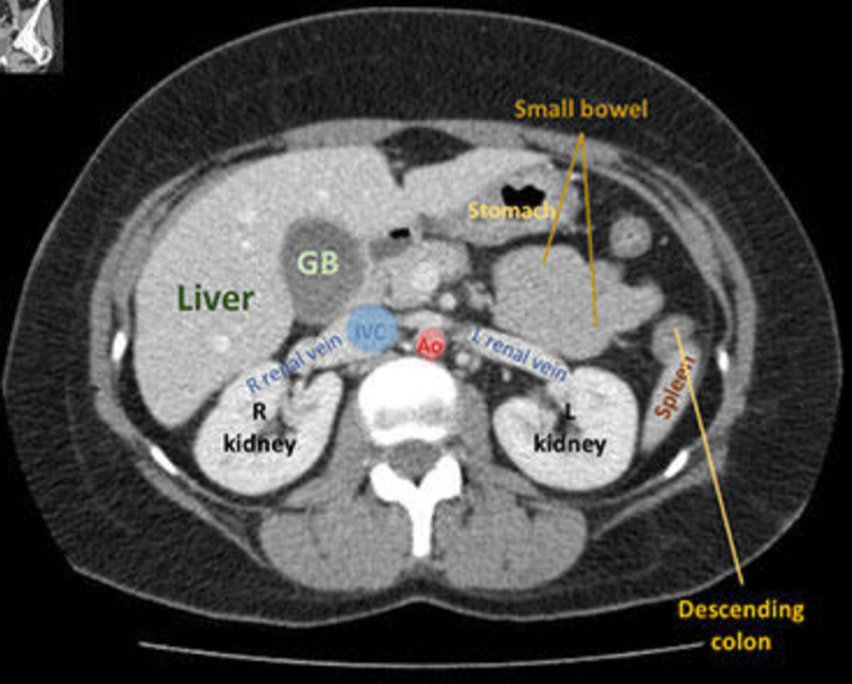

Nævn basale organer på CT:

A